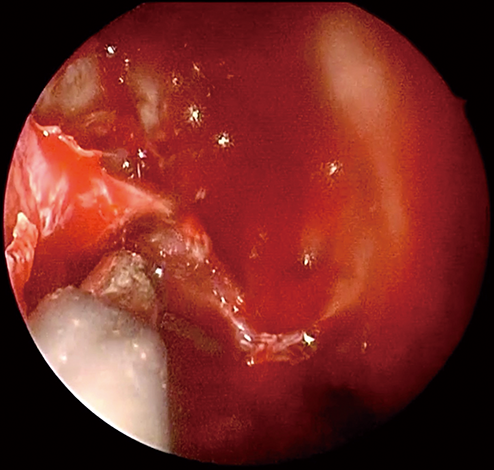

使用イメージ